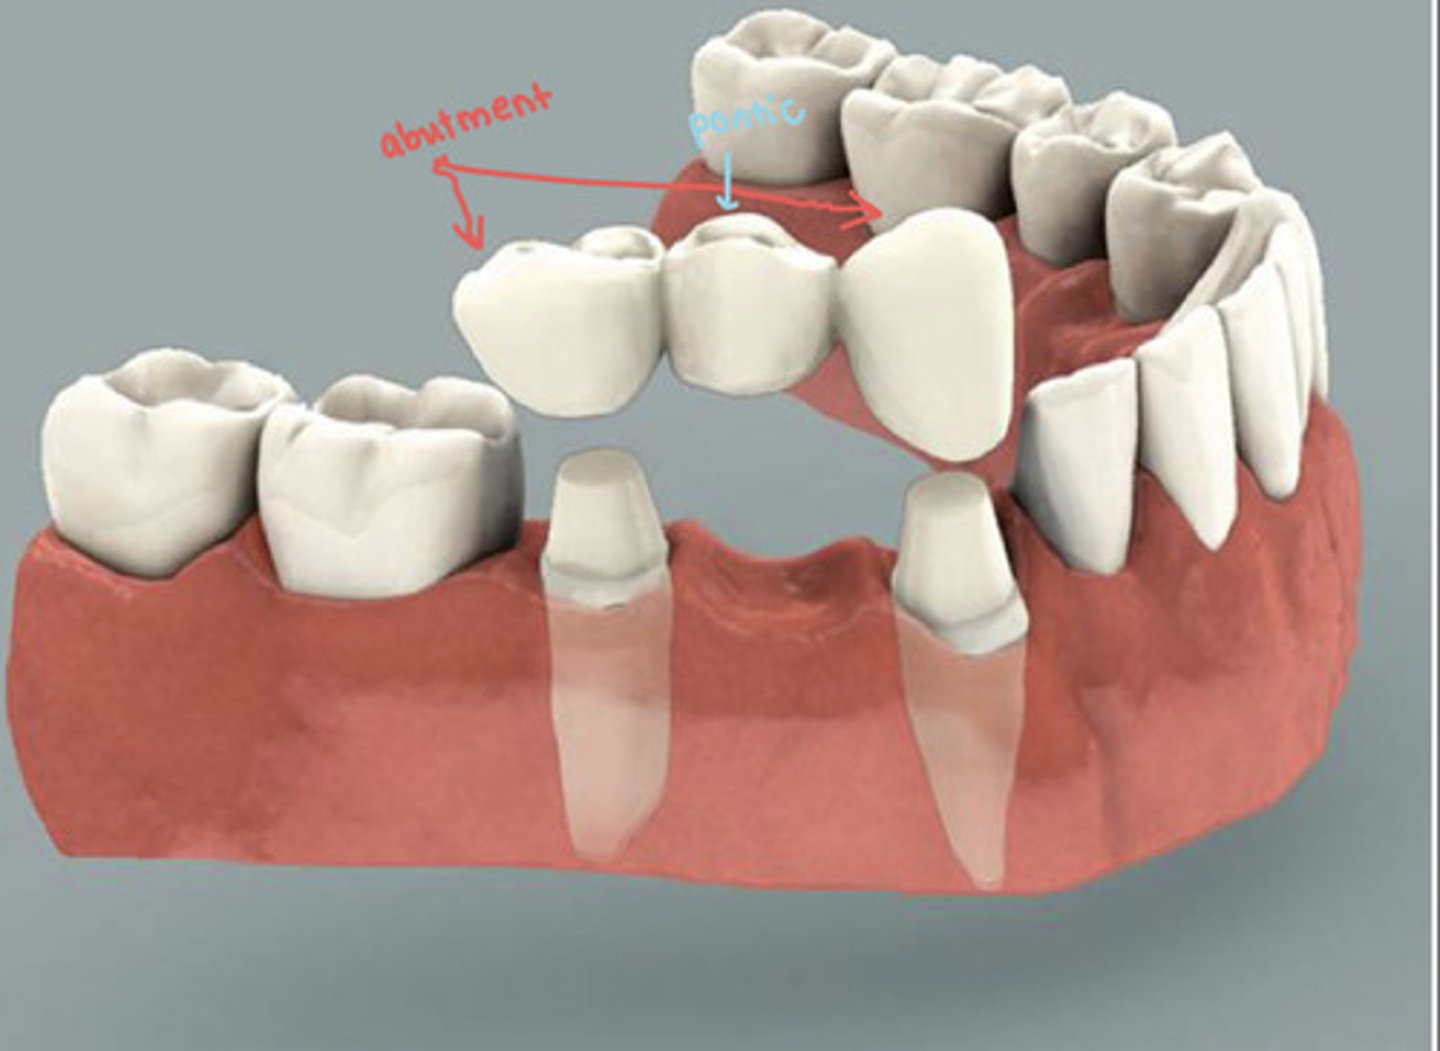

dental bridges

dental bridge radiographically?